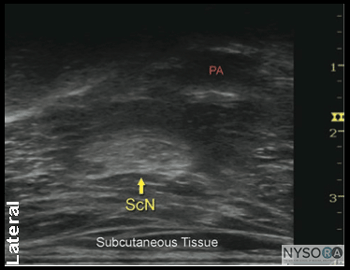

General Considerations Performance of a sciatic block above the popliteal fossa benefits from ultrasound guidance in several ways. The anatomy of the sciatic nerve as it approaches the popliteal fossa can be variable, and the division into the tibial nerve (TN) and common peroneal nerve (CPN) occurs at a variable distance from the crease. Knowledge of the location of the TPN and CPN in relation to each other is beneficial in ensuring the anesthesia of both divisions of the sciatic nerve. Moreover, with nerve stimulator-based techniques, larger volumes (e.g., >40 mL) of local anesthetic often are required to increase the chance of block success and rapid onset. A reduction in local anesthetic volume can be achieved with ultrasound guidance because the injection can be halted once adequate spread is documented. The two approaches to the popliteal sciatic block common in our practice are the lateral approach with patient in supine (more commonly, oblique position) and the posterior approach (Figure 2). It should be noted that with the lateral approach, the resulting ultrasound image is identical to the image in the posterior approach. Both are discussed in this chapter. Only the patient position and needle path differ between the two approaches; the rest of the technique details are essentially the same. Ultrasound Anatomy With the posterior and the lateral approaches, the transducer position is identical; thus the sonographic anatomy appears the same. However, note that although the image appears the same, there is a 180° difference in patient orientation. Beginning with the transducer in the transverse position at the popliteal crease, the popliteal artery is identified, aided with the color Doppler ultrasound when necessary, at a depth of approximately 3 to 4 cm. The popliteal vein accompanies the artery. On either side of the artery are the biceps femoris muscles (lateral) and the semimembranosus and semitendinosus muscles (medial). Superficial (i.e., toward the skin surface) and lateral to the artery is the tibial nerve, seen as a hyperechoic, oval, or round structure with a stippled or honeycomb pattern on the interior (Figure 3A and B). If difficulty in identifying the nerve is encountered, the patient can be asked to dorsiflex and plantar flex the ankle, which makes the nerve rotate or move in relation to its surroundings. Once the tibial nerve is identified, an attempt can be made to visualize the common peroneal nerve, which is located even more superficial and lateral to the tibial nerve. The transducer should be slid proximally until the tibial and peroneal nerves are visualized coming together to form the sciatic nerve before its division. (Figure 4A and B). This junction usually occurs at a distance between 5 and 10 cm from the popliteal crease but this may occur very close to the crease or (less commonly) more proximally in the thigh. As the transducer is moved proximally, the popliteal vessels move anteriorly (i.e., deeper) and therefore become less visible. Adjustments in depth, gain, and direction of the ultrasound beam should be made to keep the nerve visible at all times. The sciatic nerve typically is visualized at a depth of 2 to 4 cm.

![]() Figure 7: Simulated needle path and the proper needle tip placement to block the sciatic nerve (ScN) through the lateral approach. BFM - Biceps femoris muscle, SmM - Semimembranosus muscle. StM - Semitendinosus muscle, PA- Popliteal artery. Technique With the patient in the proper position, the skin is disinfected and the transducer positioned to identify the sciatic nerve (Figure 5). If the nerve is not immediately apparent, tilting the transducer proximally or distally can help improve the contrast and bring the nerve "out" of the background (Figure 6). Alternatively, sliding the transducer slightly proximally or distally may improve the quality of the image and allow for better visualization. Once identified, a skin wheal is made on the lateral aspect of the thigh 2 to 3 cm above the lateral edge of the transducer. Then the needle is inserted in-plane in a horizontal orientation from the lateral aspect of the thigh and advanced toward the sciatic nerve (Figure 7). If nerve stimulation is used (0.5 mA, 0.1 msec), the contact of the needle tip with the sciatic nerve usually is associated with a motor response of the calf or foot. Once the needle tip is witnessed adjacent to the nerve, and after careful aspiration, 1 to 2 mL of local anesthetic is injected to confirm the proper injection site. Such injection should result in distribution of the local anesthetic within the epineural sheath, and often, separation of the TN and CPN. When injection of the local anesthetic does not appear to result in a spread around the sciatic nerve (Figure 8), additional needle repositions and injections may be necessary. When injecting into the epineurium, correct injection is recognized as local anesthetic spread proximally and distally to the site of the injection around both divisions of the nerve. This typically results in separation of TN and CPN during and after the injection.